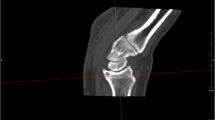

Raw DICOM data were transferred to open-source software, 3D slicer (http://www.slicer.org) [24] for analysis. DICOM data were converted to discrete 3D volumes for each acquisition time point. Each 3D volume (frame) was separately segmented to generate surface-rendered meshes (stereolithography-STL format) for each carpal bone (Fig. 1). The segmentation followed the steps described by Zhao et al. [19] and time taken for segmentation of each is estimated between 8 and 10 h.

Scaphoid positions during wrist ulnar to radial deviation, with its relation to the radius. The scaphoid is segmented at each time point and saved as a 3-dimensional mesh in the stereolithography (STL) format. The image shows the relationship of the scaphoid to the radius. Every 4th consecutive frame/time point of a single representative normal wrist is depicted